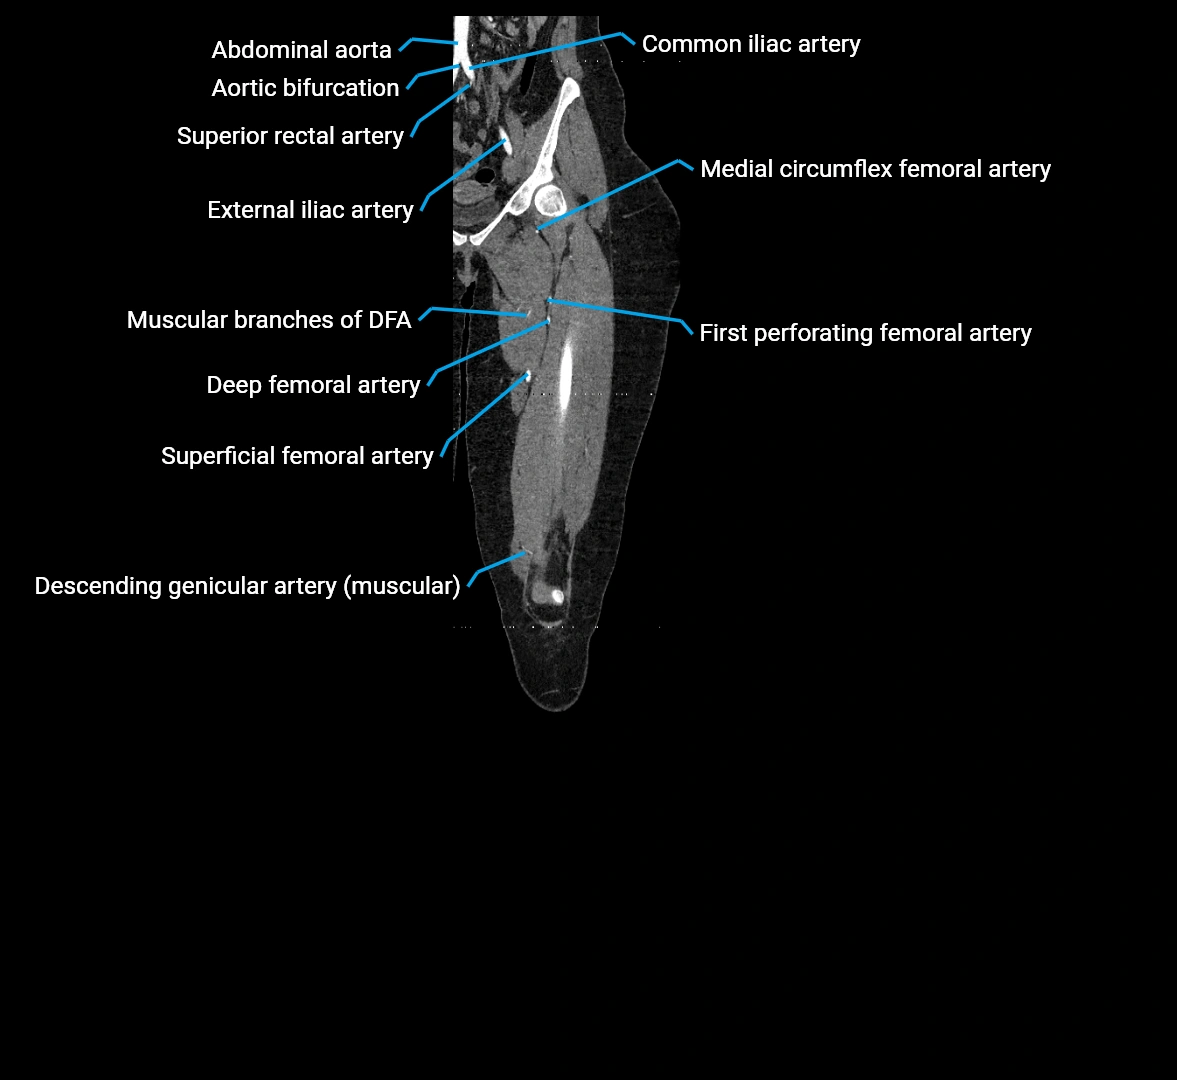

The abdominal aorta is the continuation of the thoracic aorta, beginning at the level of the aortic hiatus of the diaphragm (T12 vertebra) and terminating at the level of the L4 vertebra where it bifurcates into the right and left common iliac arteries. It lies slightly to the left of the midline and courses anterior to the vertebral bodies, surrounded by the retroperitoneal structures of the abdomen.

The abdominal aorta gives off numerous visceral and parietal branches, supplying the abdominal organs, pelvic structures, and lower limbs. It is the main conduit of oxygenated blood from the heart to the abdomen and lower body. The aorta is clinically significant as the common site of aneurysm, dissection, atherosclerosis, and traumatic injury.

Branches

• Unpaired visceral branches: celiac trunk, superior mesenteric artery (SMA), inferior mesenteric artery (IMA)

• Paired visceral branches: middle suprarenal arteries, renal arteries, gonadal arteries (testicular or ovarian)

• Parietal branches: inferior phrenic arteries, lumbar arteries, median sacral artery

• Terminal branches: right and left common iliac arteries

CT Appearance

Contrast-enhanced CT (CTA):

• Gold standard for abdominal aortic imaging

• Provides excellent detail of lumen, wall, aneurysm, thrombus, and branch vessels

• Multiplanar and 3D reconstructions help in aneurysm measurement, stent graft planning, and dissection evaluation

• Detects acute rupture, traumatic injury, or occlusion with high sensitivity